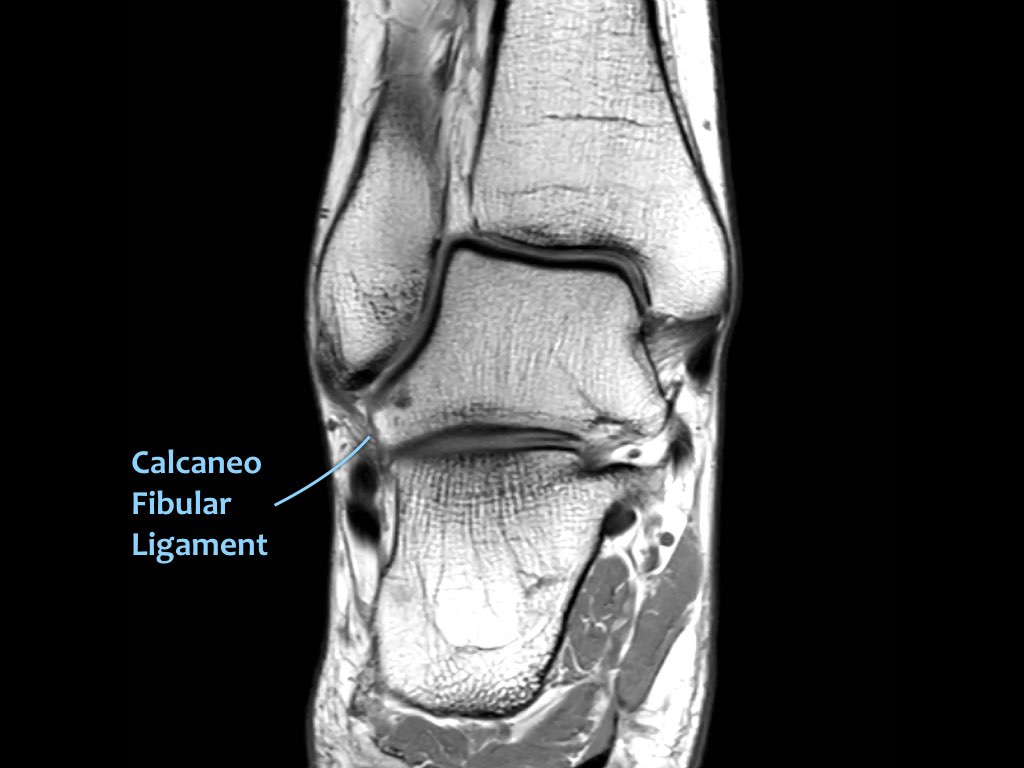

ATFL

Có ba dây chằng ở phía ngoài:

- Dây chằng sên mác trước (anterior talofibular ligament – ATFL)

- Dây chằng gót mác (calcaneofibular ligament – CFL)

- Dây chằng sên mác sau (posterior talofibular ligament – PTFL).

Dây chằng ATFL chạy từ mắt cá ngoài ra phía trước đến bờ ngoài của xương sên.

Dây chằng này có hướng nằm ngang và được quan sát rõ nhất trên ảnh cắt ngang.

Đây là dây chằng bị tổn thương thường gặp nhất ở cổ chân và cũng là dây chằng đầu tiên bị tổn thương ở phía ngoài.

Điều này có nghĩa là khi dây chằng CFL hoặc PTFL bị tổn thương, rất có khả năng dây chằng ATFL cũng đã bị tổn thương.